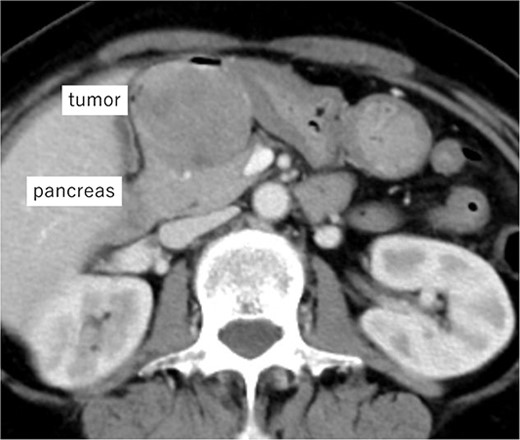

A 62-year-old woman presented at our hospital with a primary complaint of orbital pain for the past month. Esophagogastroduodenoscopy showed a duodenal ulcer, whereas a biopsy revealed presence of spindle cells. Immunohistochemistry positively identified c-kit, CD34 and DOG1 and the tumor was diagnosed as a D-GIST. Computed tomography (CT) showed a 5 cm large mass with a contrast effect on the posterior wall of the duodenal bulb and pancreatic head invasion (Fig. 1). Robot-assisted distal gastrectomy was planned. In case the invasion in the pancreatic head could not be detached, an open pancreatoduodenectomy (PD) was to be performed. The operative findings were as follows:

Imaging of the tumor. Contrast-enhanced CT showing a 5 cm large mass with contrast effect on the posterior wall of the duodenal bulb and pancreatic head invasion.